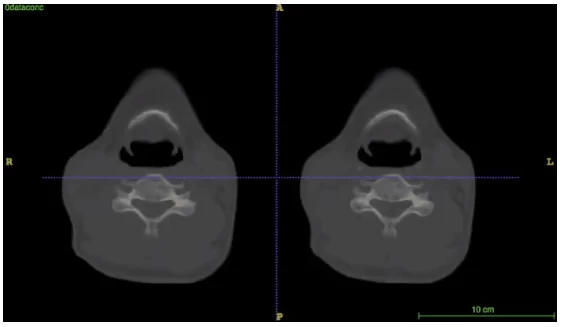

图1:器官神经网络危及器官分割结果

图1为器官神经网络危及器官分割结果,其中绿色为医生标注,红色为器官神经网络预测结果,黄色表示标注和预测重合,结果显示高度一致。

从图2的动态效果图上,可以更清晰地在三维CT所有切片上看到器官神经网络预测和医生标注的比较,其中左边显示的是医生标注,右边显示的是器官神经网络预测结果。